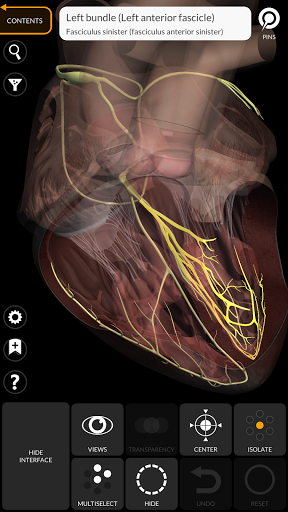

"Anatomy 3D Atlas" cho phép bạn nghiên cứu giải phẫu người theo cách dễ dàng và tương tác.

Thông qua giao diện đơn giản và trực quan, bạn có thể quan sát mọi cấu trúc giải phẫu từ mọi góc độ.

Các mô hình giải phẫu 3D đặc biệt chi tiết và có kết cấu lên đến độ phân giải 4k.

MÔ HÌNH GIẢI PHẪU 3D

• Hệ thống tim mạch

• Hệ thống thần kinh

TÍNH NĂNG •

• Xoay và phóng to từng mô hình trong không gian 3D

• Tùy chọn ẩn hoặc cô lập một hoặc nhiều mô hình đã chọn

• Chức năng trong suốt

• Bằng cách chọn một mô hình hoặc một ghim, thuật ngữ giải phẫu liên quan sẽ hiển thị